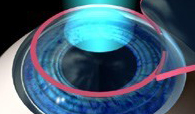

Método de aplicação do Laser nas camadas intermediárias da córnea após a preparação, utilizando-se o microcerátomo automatizado, de uma lentícula que posteriormente recobrirá a área tratada sem necessidade de pontos. Pode corrigir graus mais elevados e geralmente não há necessidade do uso de lente de contato no pós-operatório, sendo a recuperação visual mais rápida.